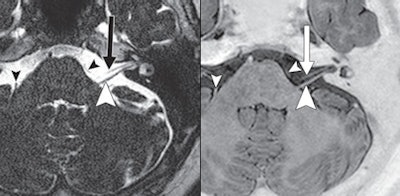

| A 70-year-old woman with lung cancer and no brain metastasis. The STIR MRI (right) shows seventh (arrow) and eighth (large arrowhead) cranial nerves and transverse pontine vein. T2-weighted MRI also shows seventh (arrow) and eighth (large arrowhead) nerves and transverse pontine vein (small arrowheads). Images courtesy of the American Journal of Roentgenology. |

While the researchers described the visualization of the sixth and lower cranial nerves as worse than that of the other nerves, they also concluded there was no statistically significant difference between the two techniques, as measured by the reader scores.

In their comparison, they found that STIR and T2-weighted MR images were almost identical, with all image ratings for the fifth, seventh, and eighth cranial nerves rated 3 (good results). On STIR images, 72 (77%) sixth cranial nerves were graded 3, while 20 (21%) cranial nerves were graded 2, and two (2%) cranial nerves were rated as 1. T2-weighted images achieved a 3 rating for 70 (74%) nerves, 20 (21%) cranial nerves were graded 2, and four (4%) cranial nerves received a 1.